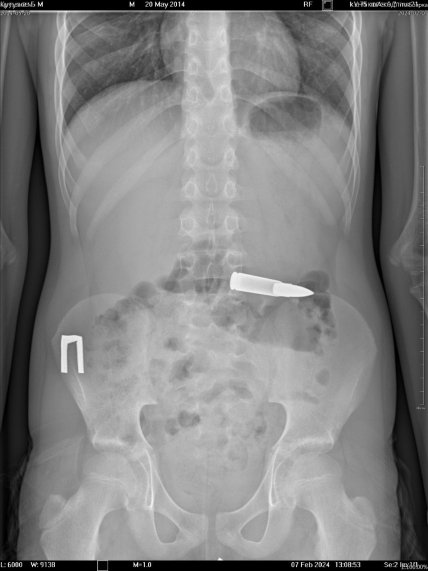

Так, дитину до лікарні доправили батьки. Після комплексного обстеження лікарі зрозуміли, що у шлунково-кишковому тракті пацієнта знаходиться стороннє тіло, в якому вдалося розпізнати кулю.

На рентген-знімках фахівцям вдалося побачити боєприпас, який перебував у горизонтальному положенні. На щастя оперативному втручанню ніщо не заважало і тому медики вдало вилучили сторонній предмет із шлунково-кишкового тракту дитини.